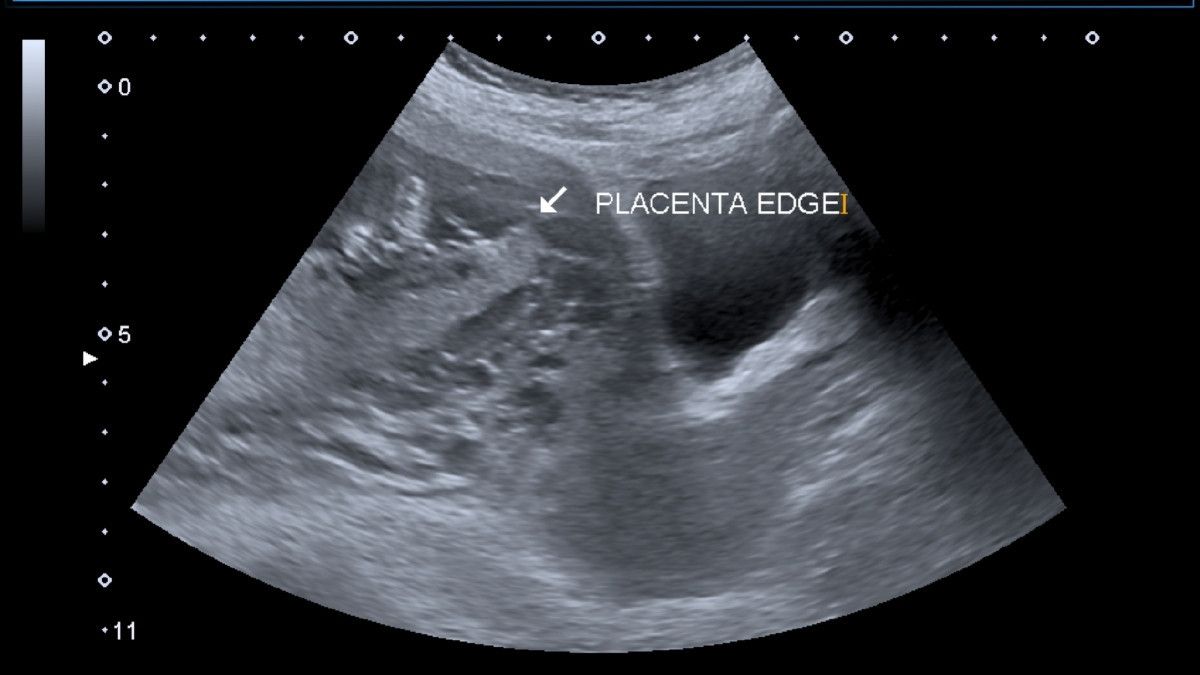

Ketika ibu hamil melakukan pemindaian ultrasound pada trimester kedua atau ketiga, placental lake kemungkinan akan terlihat. Pada hasil pemindaian, danau plasenta ini pun tampak seperti area hitam di sekitar atau mengelilingi janin.

Placental lake merupakan genangan darah ibu hamil yang terdapat di dalam plasenta, sehingga pada pemindaian ultrasound terlihat sebagai area hitam. Mengenai penyebabnya, hingga saat ini belum banyak ahli yang bisa mengungkapkan secara pasti kenapa plancetal lake bisa muncul.

Sementara ada beberapa ahli yang percaya bahwa danau plasenta adalah ruang vaskular avil, seperti tercantum di jurnal penelitian tahun 2013 yang dimuat di Nepal Journals Online. Ruang vaskular avil sendiri adalah ruang di dalam plasenta yang tidak memiliki jaringan plasenta, melainkan hanya pembuluh darah yang mengalir.

Di samping itu, sebuah penelitian berjudul “Are Placental Lakes of Any Clinical Significance?” menyebutkan bahwa placental lake dapat terjadi ketika plasenta sedikit lebih tebal daripada plasenta pada umumnya.